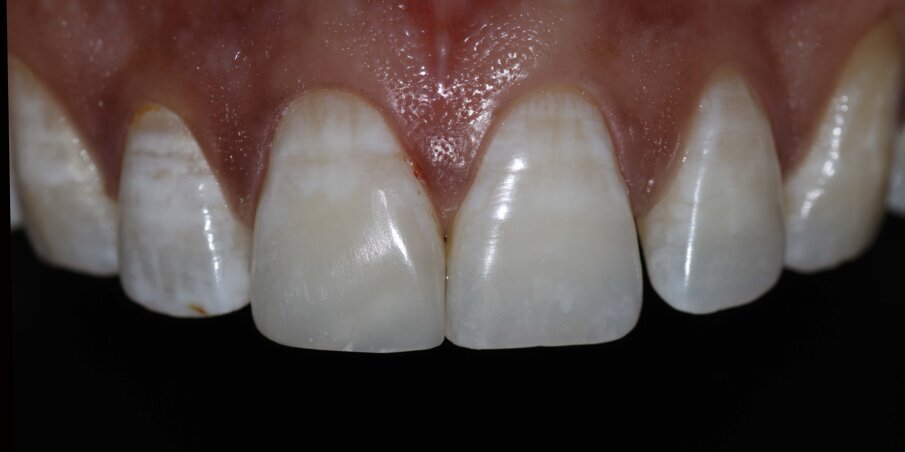

Rubber dam isolation with floss tie ligature was carried out to provide absolute isolation required for the bonding protocol. A 2mm wide bevel was given with a diamond point and finished with finishing discs involving the enamel and dentin on the buccal surface of the fractured tooth. The palatal portion of the fracture line was only smoothened to remove any overhanging enamel. The tooth was etched with 37% Phosphoric Acid (D tech) for 20 seconds. After thorough rinsing with water and light air-drying, two coats of Universal Bonding Agent (Single Bond Universal, 3M ESPE) was applied, air thinned and photocured for 20 seconds. Palatal shell was made with A2 Enamel (Filtek Z350XT) using a mylar strip and index finger held palatally for support. At this stage, the Unica Anterior Matrix (Polydentia) was adapted and secured by pulling the palatal wings and placing an interdental wedge. A2 Enamel was then applied and compacted against the matrix mesially to form the mesial surface of the restoration. Once we have an adequate ‘box’ with tight interproximal contact, it becomes relatively easy to finish the final layering. In this case, A2 Dentin, A2 Body, and A2 Enamel shades were used to complete the restoration. White opaque tints were also added before the final enamel layer to mirror the white spot characterisation of the adjacent tooth. The final enamel layer was contoured to match the mesial transitional line angle of 21 using a Mylar Pull Through method against the cured mesial wall with good contact already established with the Unica. Finishing was carried out with finishing discs (Shofu Snap-on Discs) and Soflex Spirals (3M ESPE). Polishing was done with Prisma Gloss polishing paste (Dentsply) and a rubber.

Fig 11: Tight proximal contact achieved. Final intraoral picture after finishing and polishing

Fig 12: Final Smile